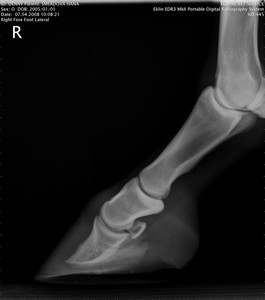

RTG Pravá přední (07.04.2008)